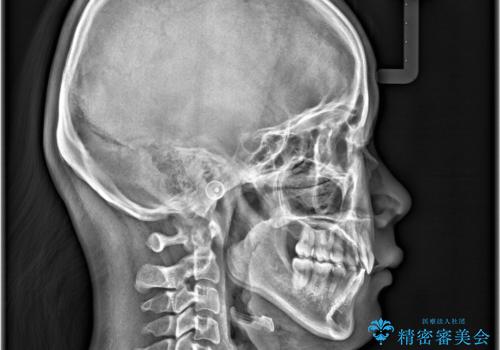

- 「歯のでこぼこと捻じれを治したい」を主訴に来院された患者様です。矯正検査の結果、上顎前歯がかなり唇側傾斜という結果になったので上下左右4番を抜歯をしワイヤー矯正で治療を行いました。

抜歯矯正でしたが順調に治療が進み2年で矯正治療を終えることが出来ました。歯のでこぼこや捻じれが治り、口元も下がって患者さんも大変満足されていました。